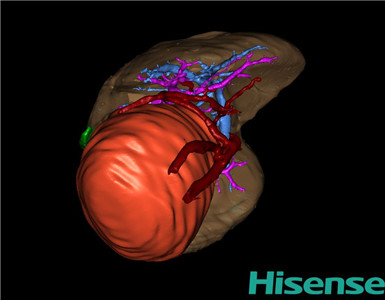

CT结果输入海信CAS系统后行3D重建及手术规划后,于2016-2-16全麻下行“腹膜后肿瘤切除术”治疗。

术前三维重建及手术方案设计:

将0.625mm双源薄层CT资料的静脉期和动脉期Dicom格式文件导入海信CAS系统。

通过调节窗宽窗位调整CT序号,对肿瘤、肝实质,胆囊,下腔静脉,肿瘤,肝动脉、门静脉及肝静脉等进行三维重建;系统自动计算肿瘤体积和肝脏体积。

模拟手术操作,自动计算切除肿瘤体积。肝脏体积为459.7ml,肿瘤体积为363.7ml,肿瘤体积为肝脏体积的79.12%,通过比对3-岁正常肝脏体积为248.41±85.99ml,通过术前模拟手术,精准判断切除后剩余肝脏体积能耐受,避免肝衰竭发生。

术前三维重建:

重建图片